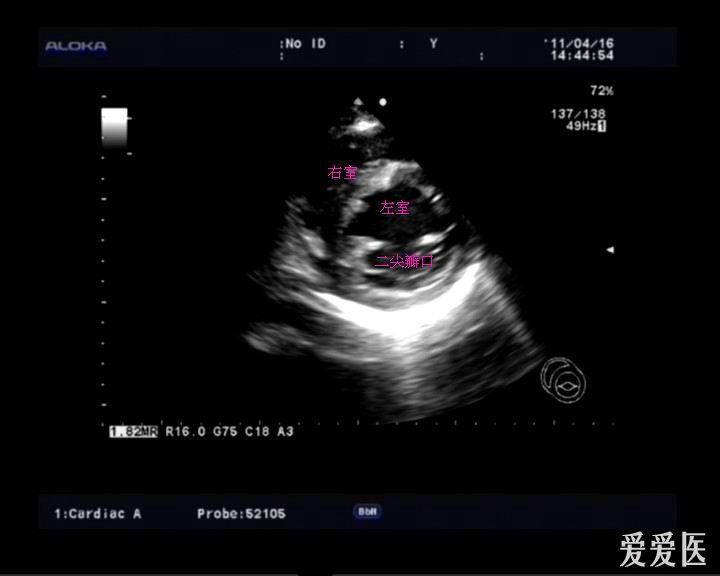

3心尖四腔心切面心尖三腔心切面二维超声2.2心尖

心不够饱满,可以上翘下压适当调整,或者,继续逆时针转,打出三腔心之后

四腔心层面